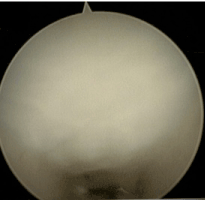

The endoscope should hug the underside of the transverse carpal ligament (TCL) and use the leading edge of the device to push synovium out of the way. Transverse fibers of the ligament should be the only thing visualized in the viewing portal of the device (Figure 3). Defining the distal edge of the TCL is assisted by using a digit from the non-instrument hand to ballot in the area of the distal edge and it is usually 30 mm from the proximal edge of TCL defined at wound dissection. After release (Figure 4) the device is then reinserted to confirm complete division of the transverse carpal ligament.

Figure 4. showing post endoscopic release.